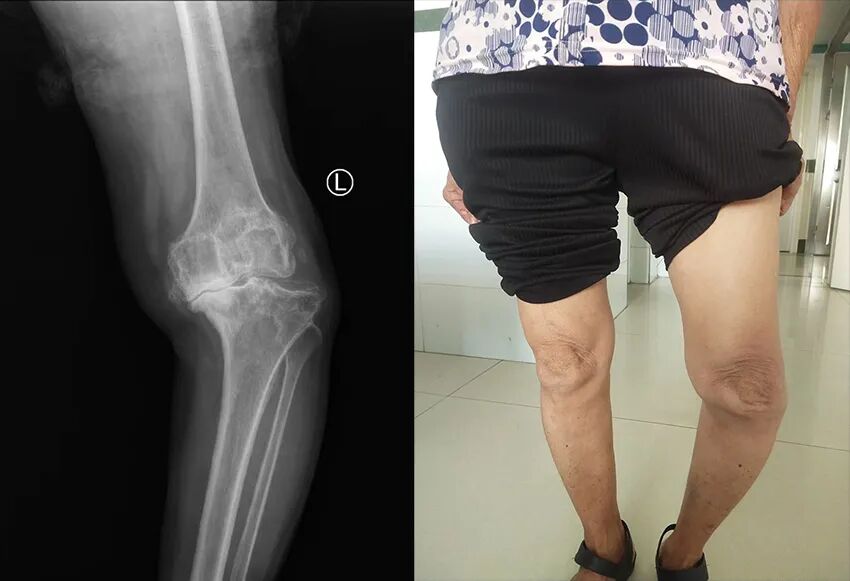

家住茂名市化州市良光鎮的龐奶奶,今年70歲,因患左膝骨性關節炎,左膝關節疼痛已長達10多年,曾自行購買藥物外擦,但效果欠佳。近半年來,左膝疼痛愈發劇烈、難以忍受并發生嚴重形變,以致于左腿不能彎曲,需要依靠拐杖行走,喪失生活自理能力,給家人帶來諸多不便。家人意識到問題的嚴重性,陪同龐奶奶輾轉了幾家醫院,均考慮老人膝關節畸形嚴重,手術難度大,風險高等原因而不愿接診。

在家人的陪同下,慕名找到湛江骨科醫院首席專家雷文黎教授就診。入院后經過全面的體格檢查、化驗、x線及CT檢查,發現左膝脛骨內髁大量缺損,脛骨、股骨及髕骨關節面周圍有大量骨贅增生,關節嚴重內翻屈曲畸形,內側副韌帶緊張,外側副韌帶松弛,關節活動受限,雷文黎教授及其團隊多次反復研究病情,應用現代最先進的3D打印技術,根據其病情制訂了三套手術方案,并對每套方案制定周密、詳細的實施計劃,第一套方案是最經濟、長期效果最好的關節表面置換術,也是難度最大,要求最精細而且最考驗醫生經驗的方案,其他兩個方案是第一個方案的替代與補充,但用的耗材比較昂貴,病人經濟負擔高。在麻醉科的全力配合下,雷文黎教授通過精準的截骨,切除關節內側、后側骨贅,并縮小脛骨平臺內側,使得內側副韌帶張力減小,內外側軟組織平衡,為實施第一個方案創造了條件,順利地為龐奶奶進行了膝關節表面置換手術,術后患者關節疼痛及畸形完全矯正,屈曲、伸直功能完全恢復。